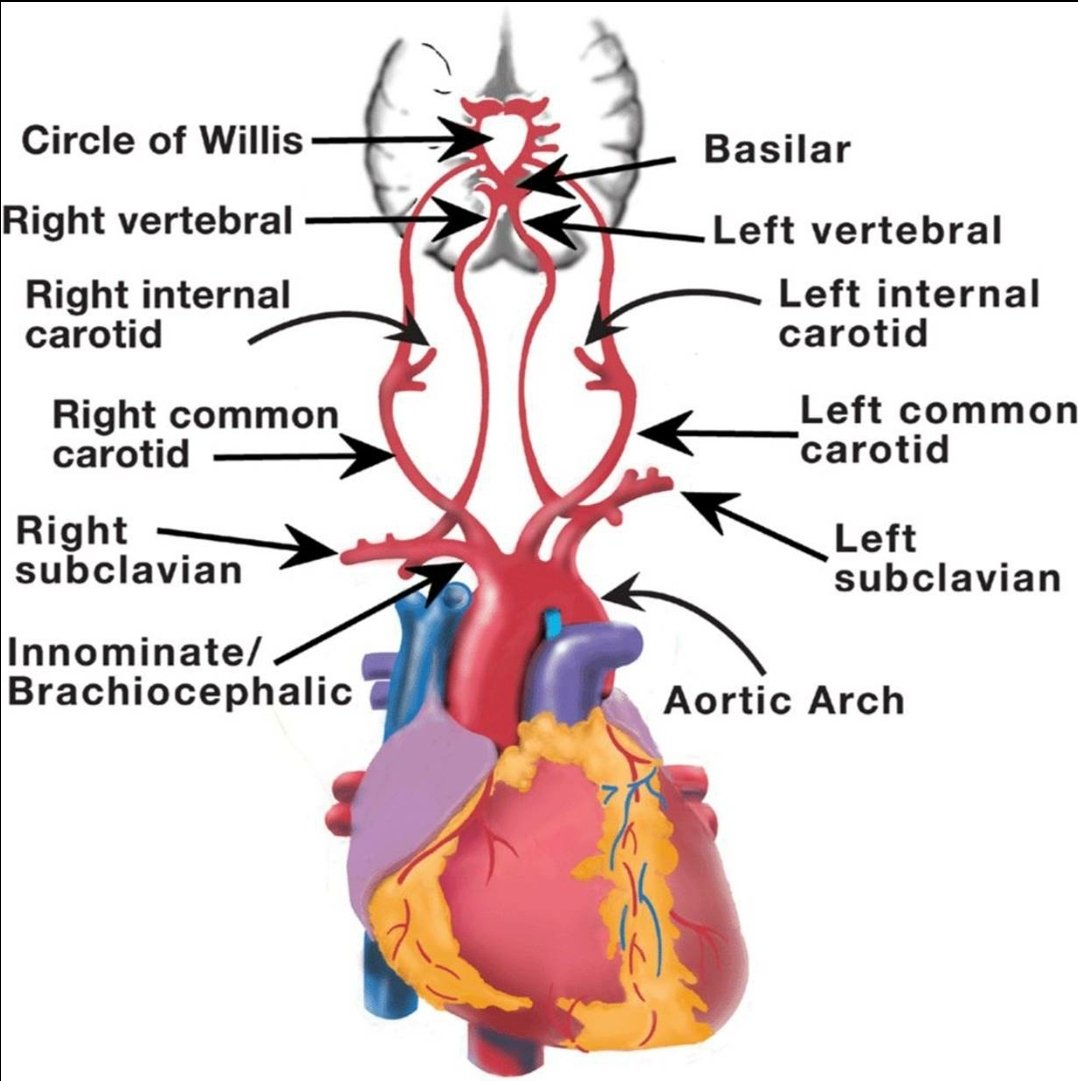

💥هي نقص في ترويه الدم للمخ اوالحبل الشوكي اوشبكيةالعين

💥بسبب (انسداد أو تضيق) في شرايين(القلب،الرقبه،الراس) الموصله للدم او الاورده المصرفه

#السكته_الدماغيه_الاقفاريه

💥الفحوصات الاساسيه

🧠اشعه مقطعيه/رنين للمخ

🧠دراسه الشرايين المغذيه للمخ

تختار حسب مكان الجلطه/وظائف الكلى/التوفر

(مقطعيه بالصبغه/رنين مغناطيسي/اشعه صوتيه للرقبه/قسطرة تداخليه)

#السكته_الدماغيه_الاقفاريه

💥العلاج

🧠علاج الجلطه الحاليه

♦️مذيب جلطات وريدي

(فقط اول ٤ ساعات ونصف)

♦️قسطرة تداخليه لسحب الجلطه من الشرايين الرئيسيه ان وجدت

(فقط اول ٦ ساعات قد تمتد بشروط)